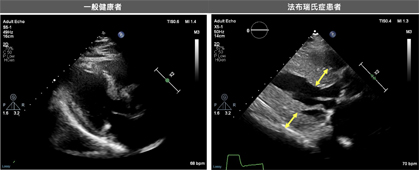

* 心臟影像學:心臟 MRI 可顯示心肌內的脂質累積,尤其是 T1值縮短(T1-shortening),對於早期診斷法布瑞氏症非常有幫助。此外,心臟超音波可評估左心室肥厚、舒張功能與瓣膜異常。

心臟超音波檢查下,相較於一般健康者,法布瑞氏症患者的心室中膈厚度與左心室後壁厚度明顯較高(黃色雙箭頭處)